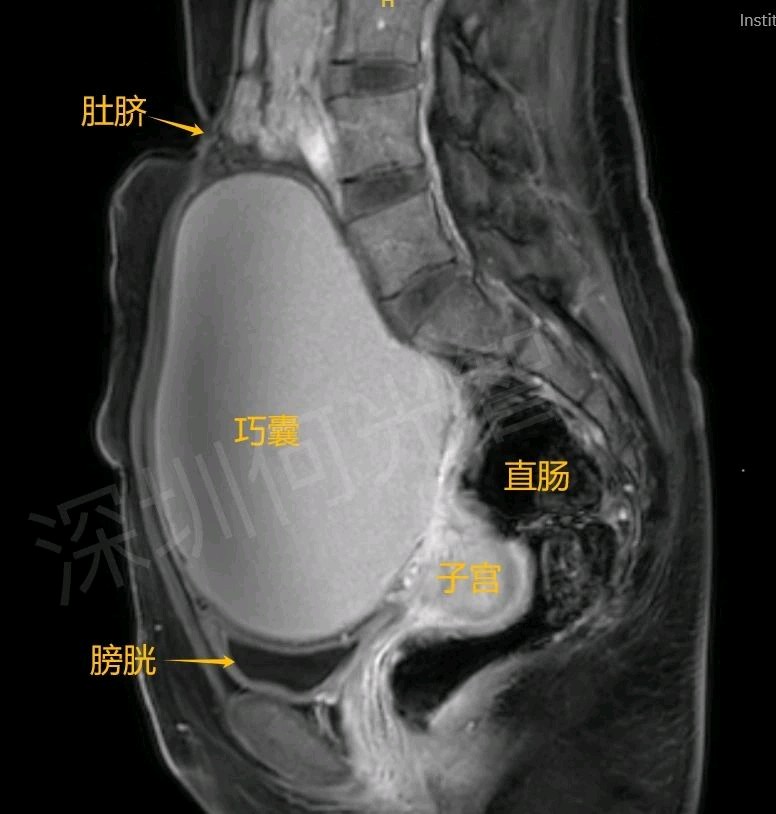

按照病友介绍,G女士通过健康160平台,很快搜索到何光智主任,并幸运地抢到预约号,按照预约时间,一个人驾车130公里,找到了光明区人民医院(西院区)。何光智主任在介入超声门诊接诊了G女士,经过详细询问病史、实验室检测、超声造影和核磁检查后明确卵巢巧克力囊肿的诊断,核磁图可见盆腔内巨大囊性包块,上缘达肚脐,压迫推挤盆腹腔脏器,长期压迫膀胱、子宫、直肠、卵巢等脏器,会影响其功能,从而带来尿频、便秘、腹痛不适。何主任表示需要及时治疗囊肿,目前治疗方法有:开腹手术剥离、腹腔镜剥离、超声引导下囊肿硬化治疗,通过分析利与弊,最后G女士选择超声引导下囊肿硬化治疗,从心理上接受介入超声“精准穿刺,创伤小,疗效好、术后恢复快、不损害卵巢功能,不造成盆腔粘连”等优点。

图3:核磁矢状面显示囊肿上缘达肚脐,向盆腔深部压迫膀胱、子宫、直肠等。